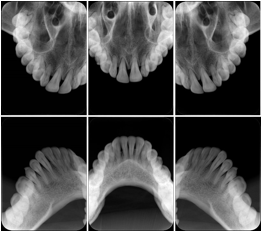

3. A patient in rural Minnesota experiences sudden vision loss and goes to a general ophthalmologist, who acquires OCT images and forwards them electronically along with a Structured Display to a retina specialist six travel hours away. The retina specialist is able to view the images in the standard layout that he is comfortable with, and to confirm that the patient has a choroidal neovascular membrane. He determines that is would be worthwhile for the patient to travel for treatment.

OCT Retinal Study with Cross Section and Navigation Structured Display

Figure OO-4. OCT Retinal Study with Cross Section and Navigation Structured Display